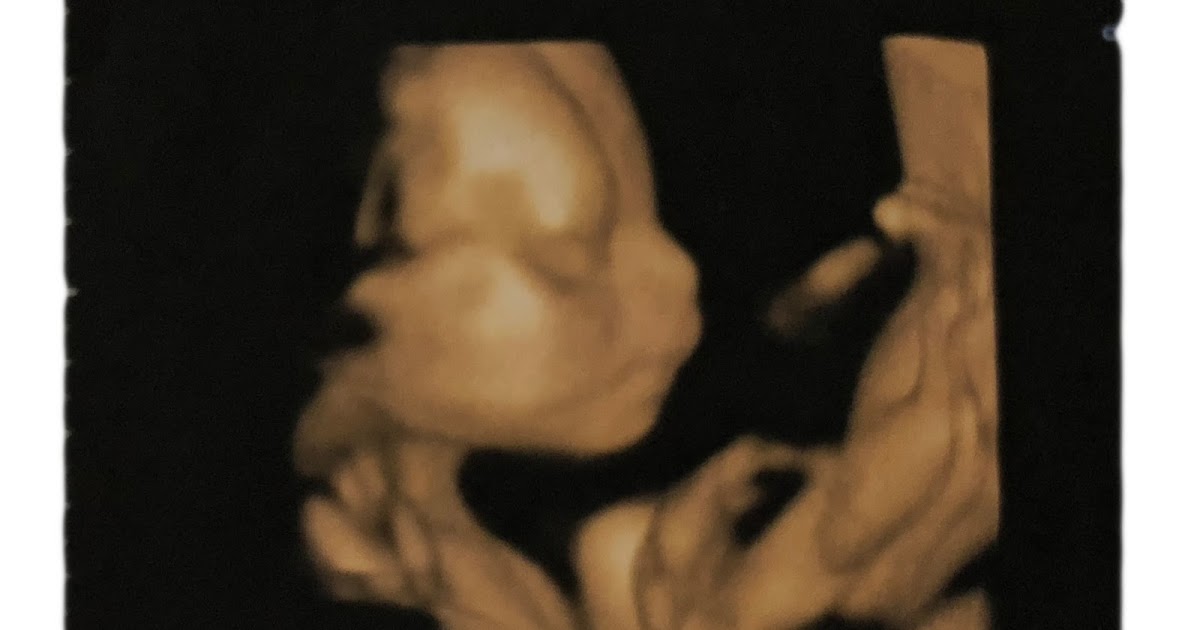

Wenn sie wissen wollen ob sie einen jungen oder ein mädchen erwarten müssen sie mindestens bis woche 17 ausharren. Ssw besonders im 3d ultraschall vorausgesetzt das kleine dreht und krümmt sich nicht so dass der arzt nichts erkennen kann. Noch bevor dein baby organe einen herzschlag oder ein gehirn hatte war das zukünftige geschlecht bereits teil der genetischen information. Ssw 17 0 tage ssw 17 1 tag ssw 17 2 tage ssw 17 3 tage ssw 17 4 tage ssw 17 5 tage ssw 17 6 tage.